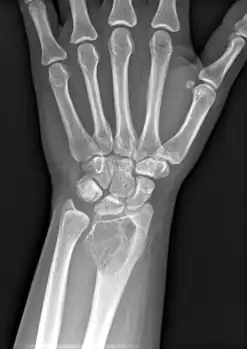

| X-ray of a giant-cell bone tumor in the head of the fourth metacarpal of the left hand | |

On X-ray, giant-cell tumors (GCTs) are lytic/lucent lesions that have an epiphyseal location and grow to the articular surface of the involved bone.[11] Radiologically the tumors may show characteristic 'soap bubble' appearance.[12] They are distinguishable from other bony tumors in that GCTs usually have a nonsclerotic and sharply defined border. About 5% of giant-cell tumors metastasize, usually to a lung, which may be benign metastasis,[13] when the diagnosis of giant-cell tumor is suspected, a chest X-ray or computed tomography may be needed. MRI can be used to assess intramedullary and soft tissue extension.